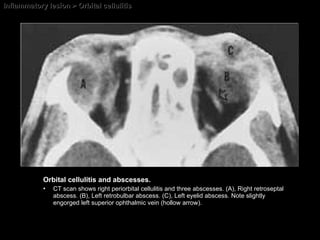

Inflammatory lesion > Orbital cellulitis Orbital cellulitis and abscesses.  CT scan shows right periorbital cellulitis and three abscesses. (A), Right retroseptal abscess. (B), Left retrobulbar abscess. (C), Left eyelid abscess. Note slightly engorged left superior ophthalmic vein (hollow arrow).